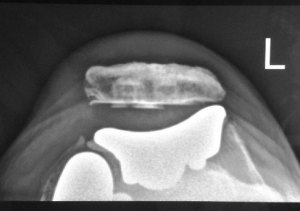

Post-operative check x-rays showed excellent alignment of the implants.